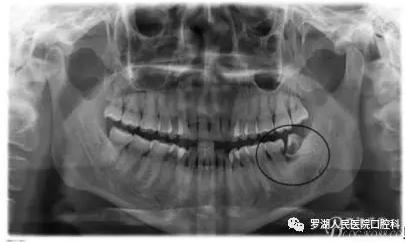

2.阻生齿

有些智齿不愿走寻常路,偏要横着长、斜着长,很容易顶到邻牙,自然会引起牙疼。

还有智齿虽然垂直长,但会躲在牙龈里,你虽然看不见它们,但疼痛难忍。